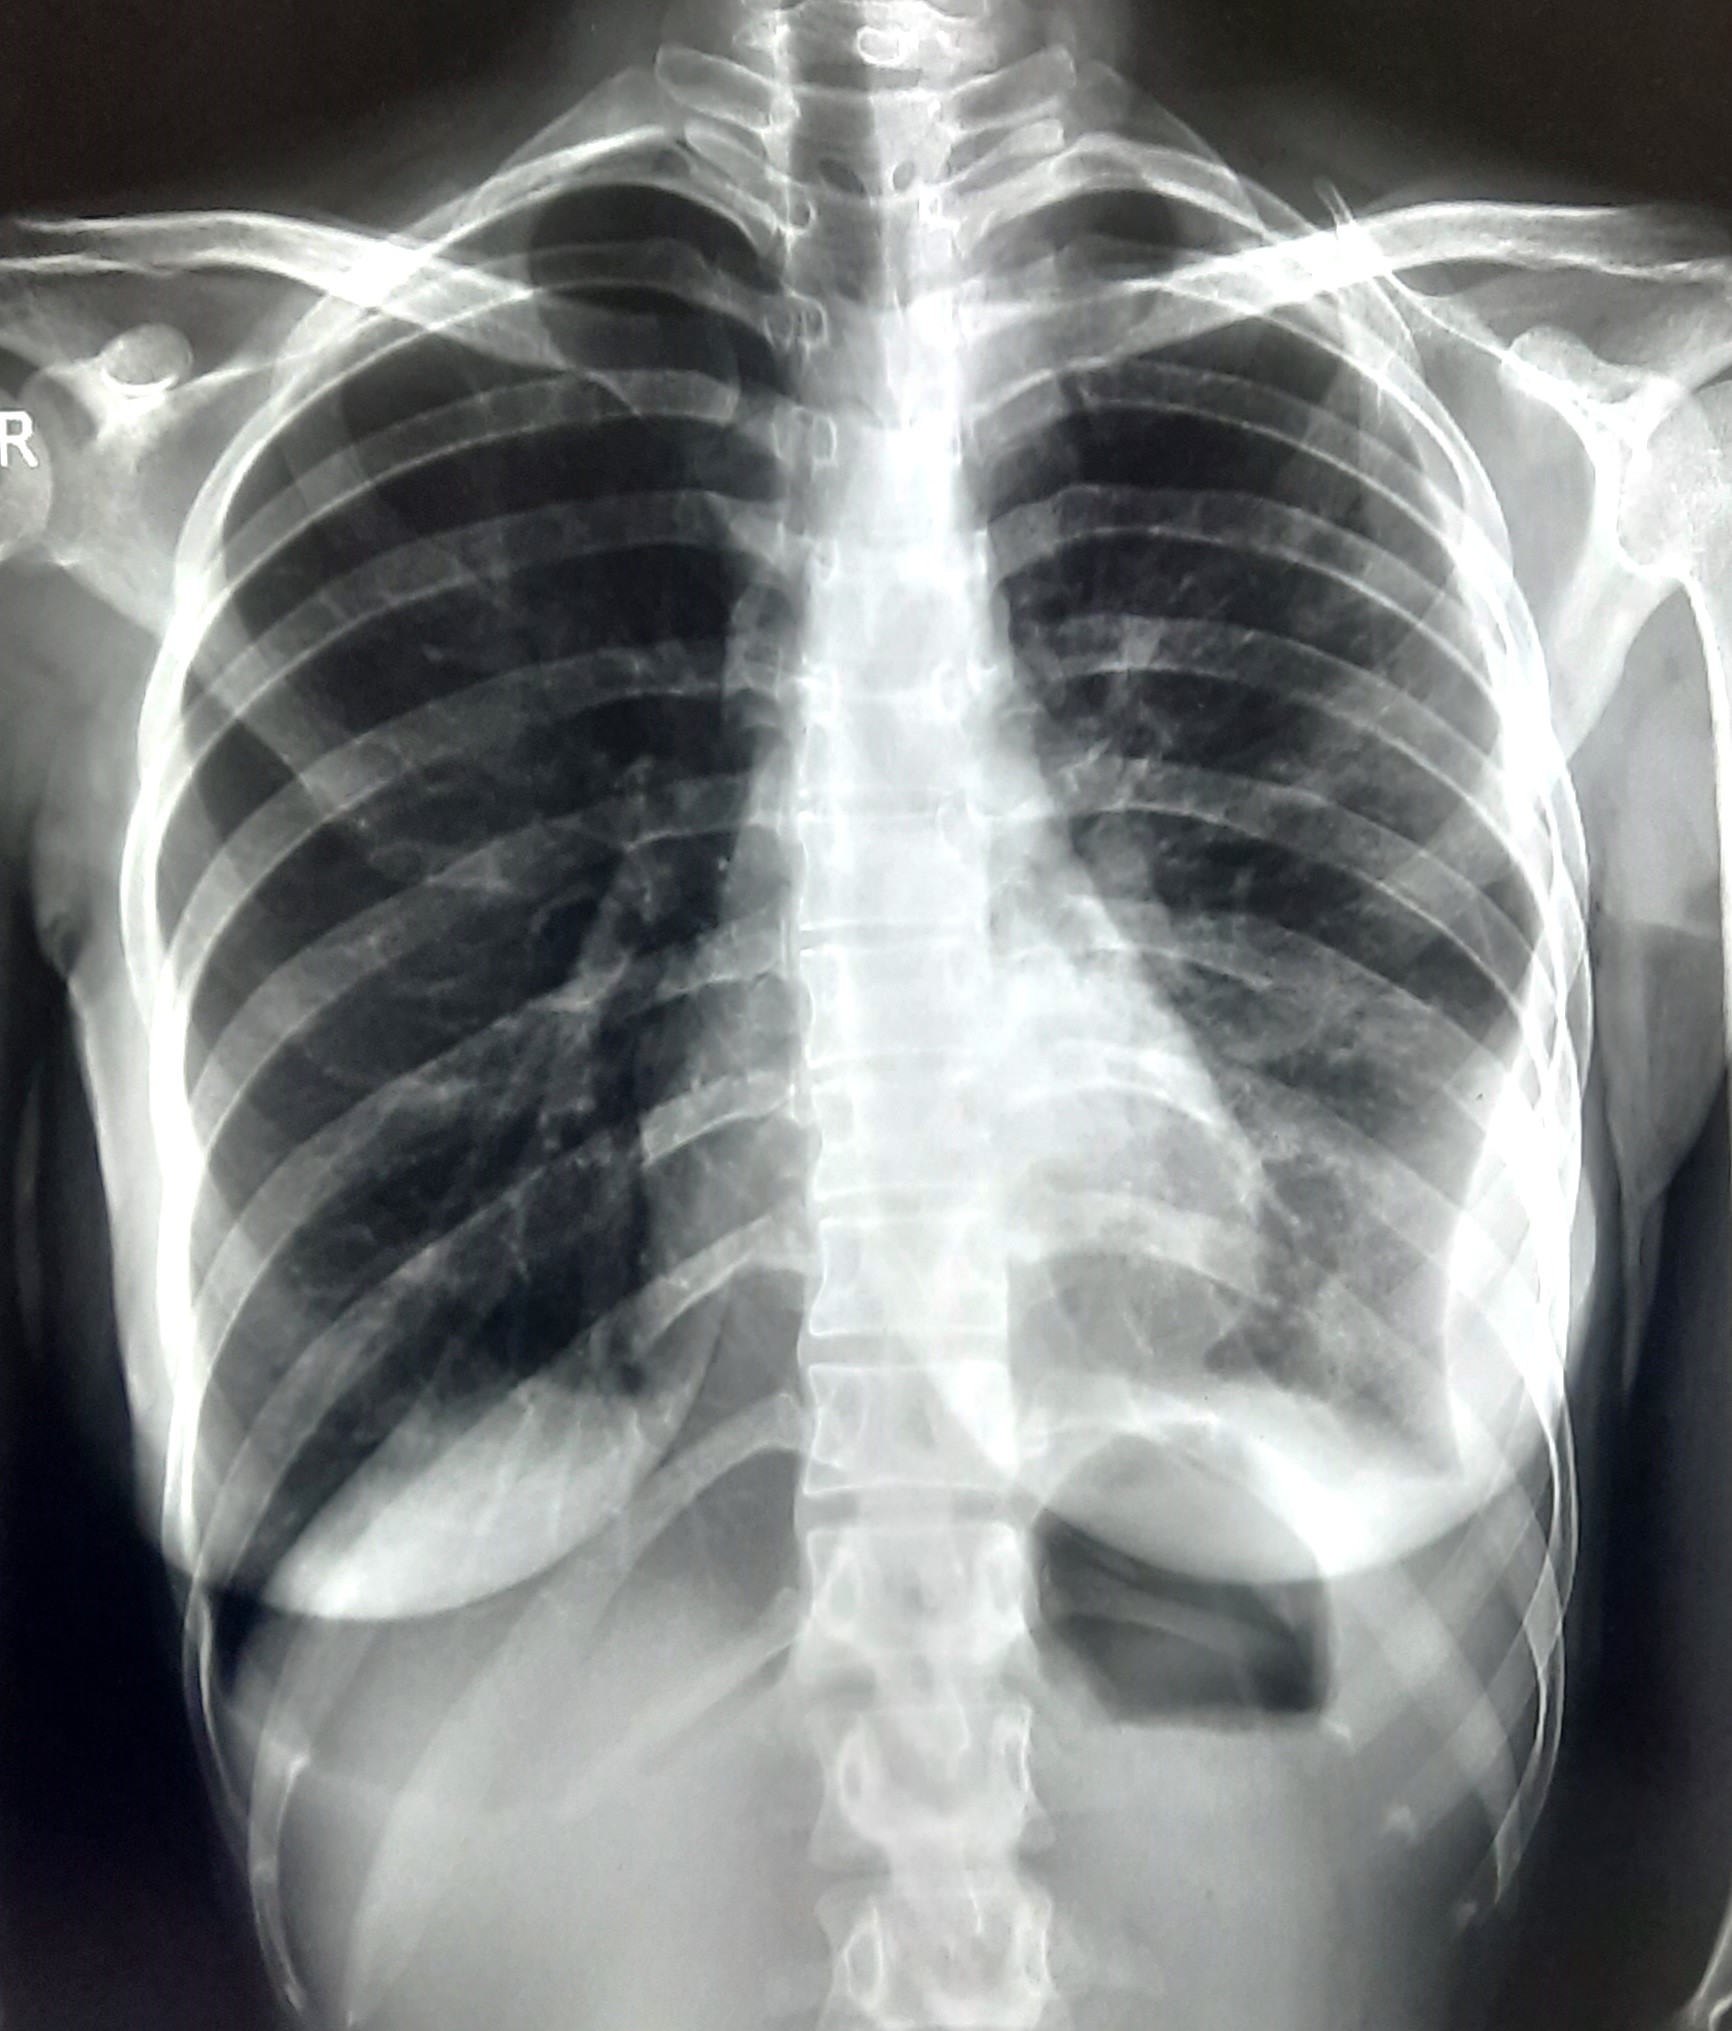

| 68 | IGGMC, Nagpur, Nagpur | P2 | 29-4404 | Gaurav Wankhede | Consent taken on Paper | 19 Yrs. |

Provisional Diag : Pulmonary Tuberculosis

Final Diag : TB Infiltration |

TB Case (Confirmed) | Bilateral Upper Zone & Mid Zone TB Infiltration | Abnormality visible on x-ray |